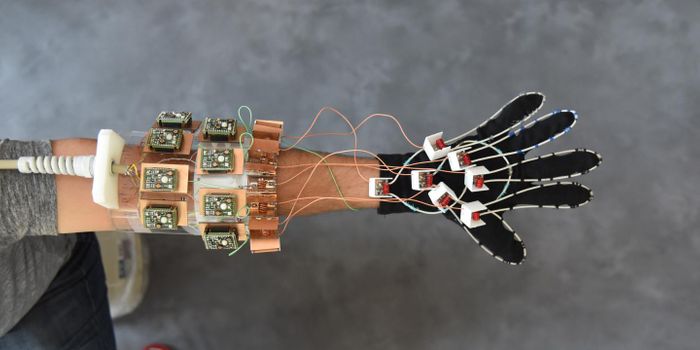

AUG 28, 2017Clinical & Molecular DXTo help Parkinson’s patients who suffer from uncontrollable tremors, London scientists have developed a device tha ...